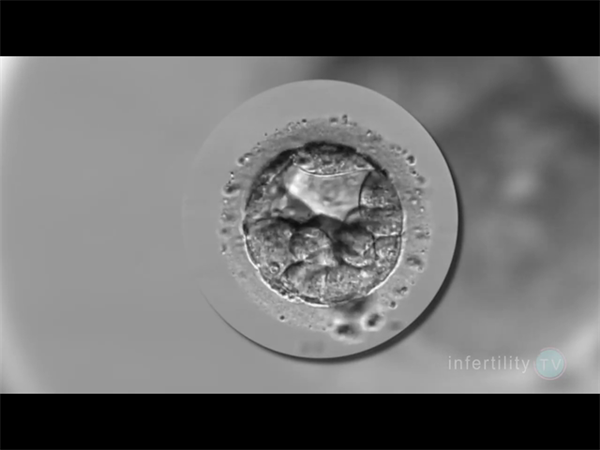

囊胚筛查主要包括三种类型的检测,PGT-A筛查胚胎的染色体数目是否正常,即非整倍体遗传学筛查;PGT-M针对特定的单基因遗传病进行筛查,例如色盲、血友病等;PGT-SR筛查染色体结构变异,例如平衡易位或者罗氏易位,其在一定程度上能减少宫外孕和胎停的可能性。但它们并不能保证筛查完全覆盖所有可能的遗传疾病,特别是当这些基因突变属于未知或新的遗传疾病时。

尽管囊胚筛查(如PGS/PGD)能够检测染色体异常和单基因遗传病,但其成功率并非100%。单基因遗传病的种类繁多,目前已知有7000多种单基因遗传病,其中4000多种已明确致病基因。因此,即使囊胚筛查正常,也不能完全排除其他未检测到的单基因遗传病。目前的基因筛查技术主要针对已知的遗传病基因进行检测,如地中海贫血、唐氏综合症等。然而,许多隐性遗传病可能尚未被完全识别或列入筛查范围。即使使用全基因组测序(NGS)技术,也无法检测到所有潜在的基因突变。

囊胚筛查正常大多不会胎停,出现这种情况大多可能是生殖免疫异常而导致的。一个胚胎,如果能够经过染色体筛查是正常的,那我们说这个胚胎应该是能够在正?;肪诚路⒂商ザ⑶易钪粘錾?,但是所移植的胚胎并没有最终发育成胎儿。因此我们基本可以断定,是生殖环境不好所导致的。